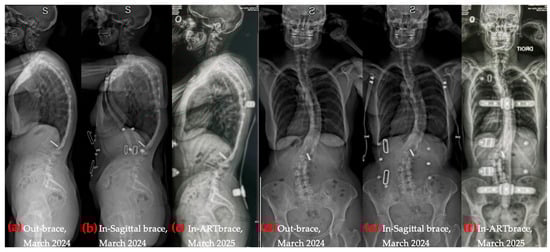

Conservative physiotherapy was first supported by a semi-rigid brace (introduced in November 2022), providing proprioceptive feedback during daily activities and sports. In January 2024, a rigid sagittal brace was added to reinforce postural correction. In February 2025, the patient was fitted with a part-time Lyon ARTBrace [34,36], a three-dimensional asymmetrical orthosis with enhanced sagittal support, intended to consolidate structural gains and maintain coronal and sagittal alignment during perimenopause, a period associated with accelerated spinal deterioration [50,51,52].

At the end of the study period, the ARTBrace had been recently delivered, and brace-integrated Schroth exercises had not yet begun. Unlike the two previous braces, which were removed during exercise, the ARTBrace was intended to be worn for about 50% of each Schroth session to enhance postural integration and proprioceptive reinforcement. Figure 3 illustrates the three orthotic devices used. Additional details regarding brace models, objectives, and wear time are provided in Appendix A.3. These outcomes align with the emerging literature supporting bracing in adults with spinal deformities [32,34,35,36,37,53,54,55,56,57].

Figure 9. Coronal and sagittal radiographic progression over time, with and without bracing. (a) Out-of-brace, sagittal X-ray; (b) In sagittal brace, sagittal X-ray; (c) In ARTbrace, sagittal X-ray; (d) Out-of-brace, coronal X-ray; (e) In sagittal brace, coronal X-ray; (f) In ARTbrace, coronal X-ray.